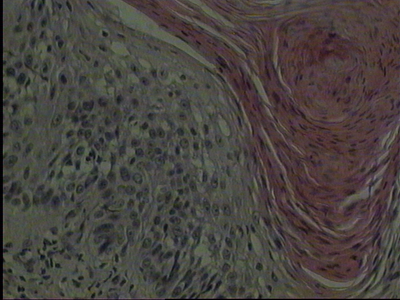

AbstractIn the following case report we describe a 66 year-old man who was presented with a squamous cell carcinoma (epithelial tumour) on the skull which grew on the scar of a previously surgically excised sarcoma (mesenchymal tumour). This is the first description of such a coincidence, which may be due to the development of a mutated stem cell colony, which differentiated in tumour cells of several lineages. Case reportThe 66 year-old patient presented to our Departments with a 3-month history of a 0.5 x 1 cm large, erythematous, ulcerated skin lesion over the medial side of a surgical scar on the left parietal side of the scalp (as shown in figure 1a). The scar (as shown in figure 1b) was due to surgical excision of a sarcoma (G2) 5 years ago [1]. At that time the dermatological examination of the patient had detected a painless solitary 3 x 5 cm large, erythematous swelling (as shown in figure 2a) and the histopathological examination (as shown in figure 2b) had detected pleomorphic mesenchymal cellular regeneration in the subcutaneous tissue with a limited nodular process. A focal fibrotic false capsule had been seen. The tissue had shown myxoid infiltration. An immune histochemical staining had revealed negative results for CD34, S100, actin, desmin and pancytokeratin staining, while labeling with the Ki67 antigen had detected a proliferation rate of 80%. The skull computer tomography prior to surgical excision of the tumour has shown a localized space-occupying lesion in the soft tissue without intracranial metastasis. The chest computer tomography did not reveal any pathological signs. The regular oncological follow-up of the patient every 6 months has detected two basal cell carcinomas over the left side of the back and the right lower limb after 2 years, which were treated surgically with elliptical excisions. The current lesion on the skull was also detected at the regular follow-up and was surgically excised. The histological examination showed orthohyperkeratosis, epidermal hyperplasia with disturbance in the cell arrangement of the lower epidermal layers associated with cellular and nuclear polymorphism. In addition, proliferation of atypical epithelial growth in the upper dermis was seen (as shown in figure 1a). The diagnosis of squamous cell carcinoma was concluded with a total depth of 0.7 mm. There was no evidence of sarcoma recurrence. The regional lymph nodes and the chest were free of lesions in imaging examinations. DiscussionSoft tissue sarcomas account for 1% of all malignancies. Approximately 60% of soft-tissue sarcomas arise in the extremities. The lower extremities are three times more often involved than the upper extremities. Further sites involved are the trunk (19%), the retroperitoneum (15%), and the head and neck (9%) [2]. Approximately 80% of head and neck sarcomas occur in adults, whereas the most common subtypes are osteosarcoma, angiosarcoma, malignant fibrous histiocytoma, and fibrosarcoma, and 10-20% occur in children, the most common subtype being rhabdomyosarcoma [3]. On the other hand, squamous cell carcinoma is the second most common malignancy of the skin after basal cell carcinoma and the skin is the most common site for squamous cell carcinoma [4]. It accounts for 20% of cutaneous malignancies and 80-90% of all head and neck cancers [5]. Sun exposure is a major risk factor for epithelial tumours, while sarcoma growth does not seem to be related to sun exposure. In our patient, skin tumours of different lineage, namely squamous cell carcinoma of epithelial (ectodermal) and sarcoma of mesenchymal (endodermal) origin, occurred at the same skin region in a period of 5 years the former developed over the scar of the latter: Such a coincidence has not been reported before. Since these lesions were the only tumors detected in this patient, a mutated stem cell colony, which is able to differentiate in cells of several lineages, could be speculated [6]. References1. WHO classification of soft tissue tumours. 2006; 10-17.2. Potter BO and Sturgis EM. Sarcoma of head and neck. Surg Oncol Clin N Am 12:379-417, 2003. 3. Sidappa KT and Krishnamurthy A. Adult soft-tissue sarcomas of the head and neck. Indian J Dermatol 48:284-288, 2011. 4. Papadopoulos O, Frantzoglou M, Chrisostomidis C, Konofaos P, Frangoulis M and Barlas G. Neglected squamous cell carcinoma of the frontal area: a clinical report. J Craniofac Surgery 17:1015-1020, 2006. 5. Hiu CS, Lin CY, Kuo TT, Kuan YZ, Chen MJ, Ho HC, Yang LC, Chen CH, Shih IH, Hong HS and Chuang YH. Malignant cutaneous tumors of the scalp: a study of demographic characteristics and histologic distributions of 398 Taiwanese patients. J Am Acad Dermatol 56:448-452, 2007. 6. Zouboulis CC, Adjaye J, Akamatsu H, Moe-Behrens G and Niemann K. Human skin stem cells and the ageing process. Exp Gerontol 43:986-997, 2008. © 2012 Egyptian Dermatology Online Journal |